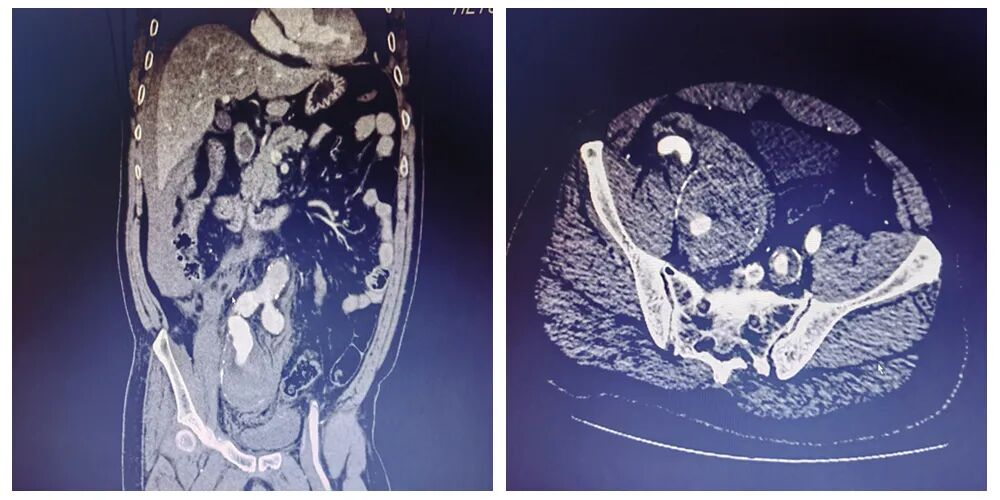

▲主动脉CTA提示右侧髂内巨大动脉瘤破裂出血